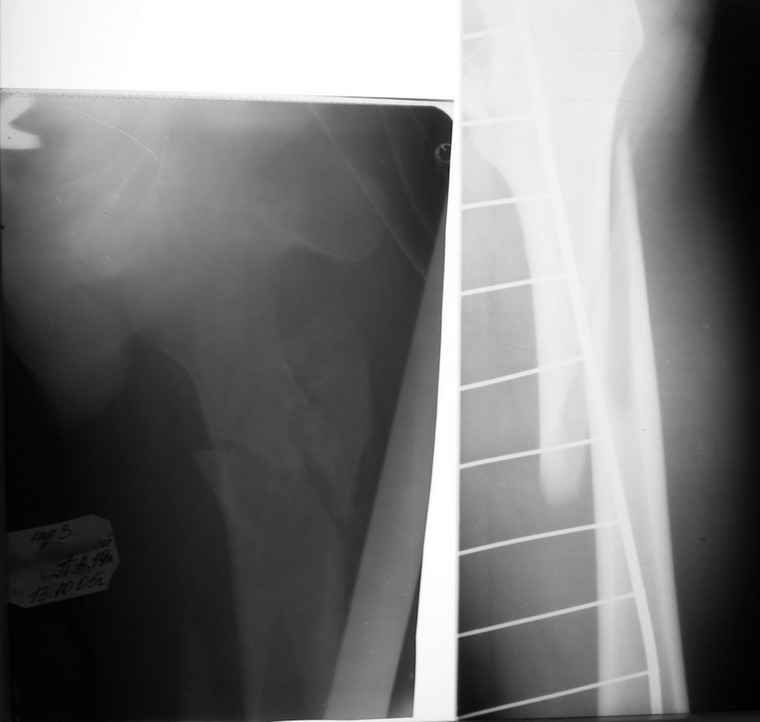

Вот снимки по свежей ситуации, парень 19 лет, длинный оскольчатый

перелом бедра от шейки до в-с/3. давно уже ходит на своих ногах.